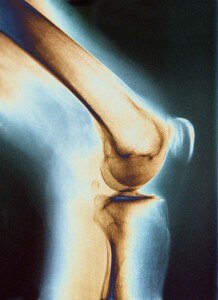

A: Joints are the areas where your bones meet. They allow your body to move. Without joints, you wouldn’t be able to walk, sit or raise your arms. At the ends of your bones are little “caps” of cartilage, a tough, smooth tissue that provides cushioning and allows movement. There is also a pool of slippery fluid, called synovial fluid, which prevents friction. Together with tendons and ligaments, these make up your joints.